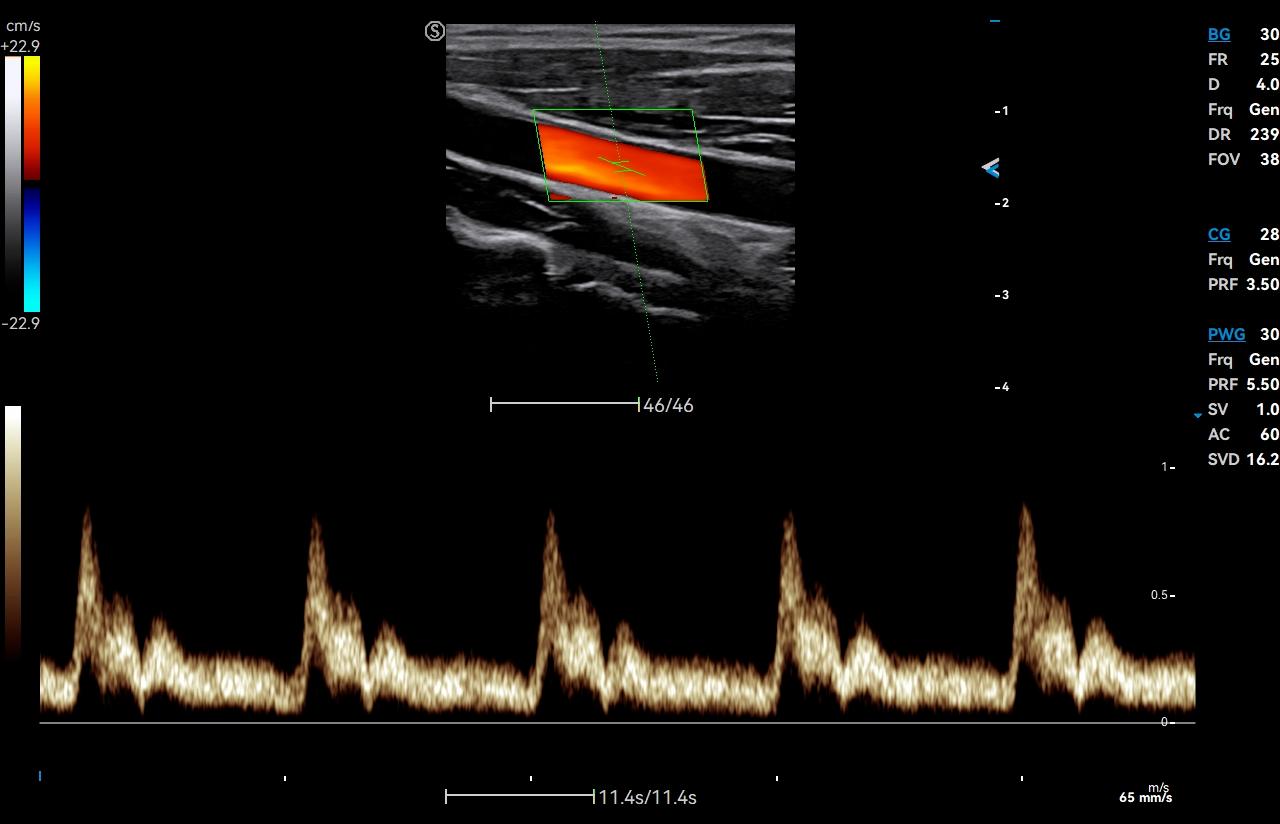

- Category: Color Doppler

Click on images to enlarge

Click on images to enlarge

VS Flow is highly sensitive to low velocity blood flow signal and especially suitable for superficial blood flow examination

Auto Flow automatically adjusts the sampling frame to better capture the blood flow signal, while Auto Fit intelligently optimizes the image display through one click